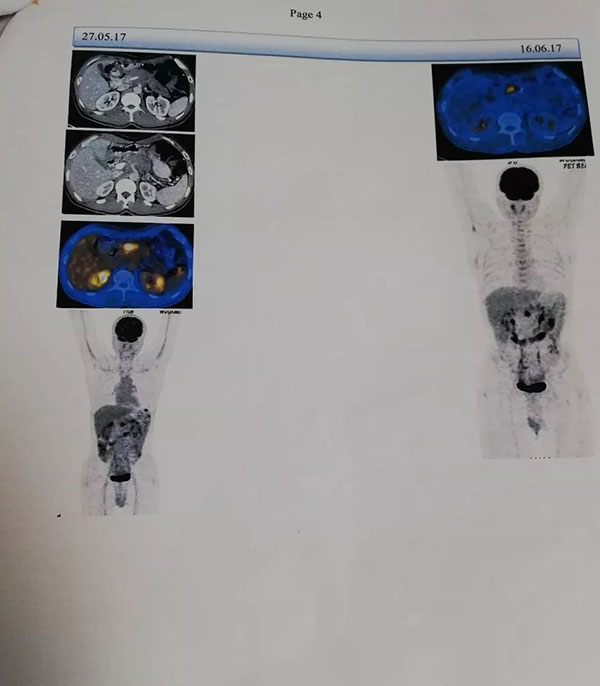

Before operation, CT showed that the pancreas was significantly larger, with an area of about 7 cm, and invaded the celiac trunk artery.

The patient’s operation is more difficult, and the patient’s family has been worried about not being able to support Haifu. After the consultation and evaluation of our team, the preliminary judgment is that Haifu can be treated.